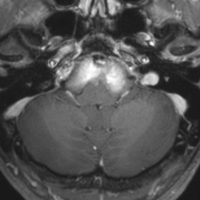

典型的な神経腸嚢胞 neurenteric cyst

左のT2強調画像で等信号,中のT2*で高信号,右はCISS画像です。

T1強調画像では,のう胞周囲の高信号の部分は半固体で,中心部の高信号はドロドロの粘液でした。基本的にガドリニウム増強はされません。まれに薄い膜状に一部が増強されることがあります。

境界明瞭は袋状の腫瘍です。椎骨動脈や脳底動脈を包み込むようにふくらんでいます。